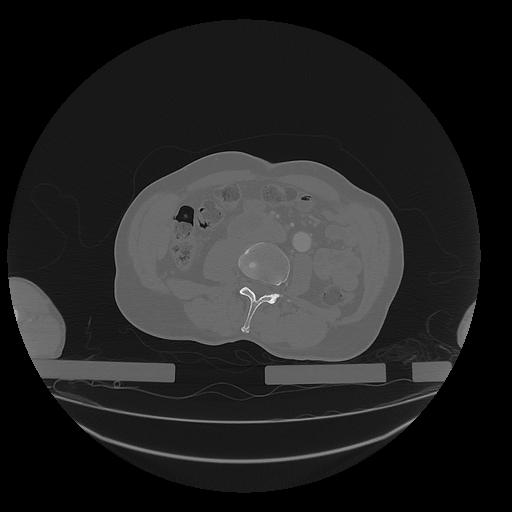

31 PULMON,CE,Vol,1.0,PULMON,,